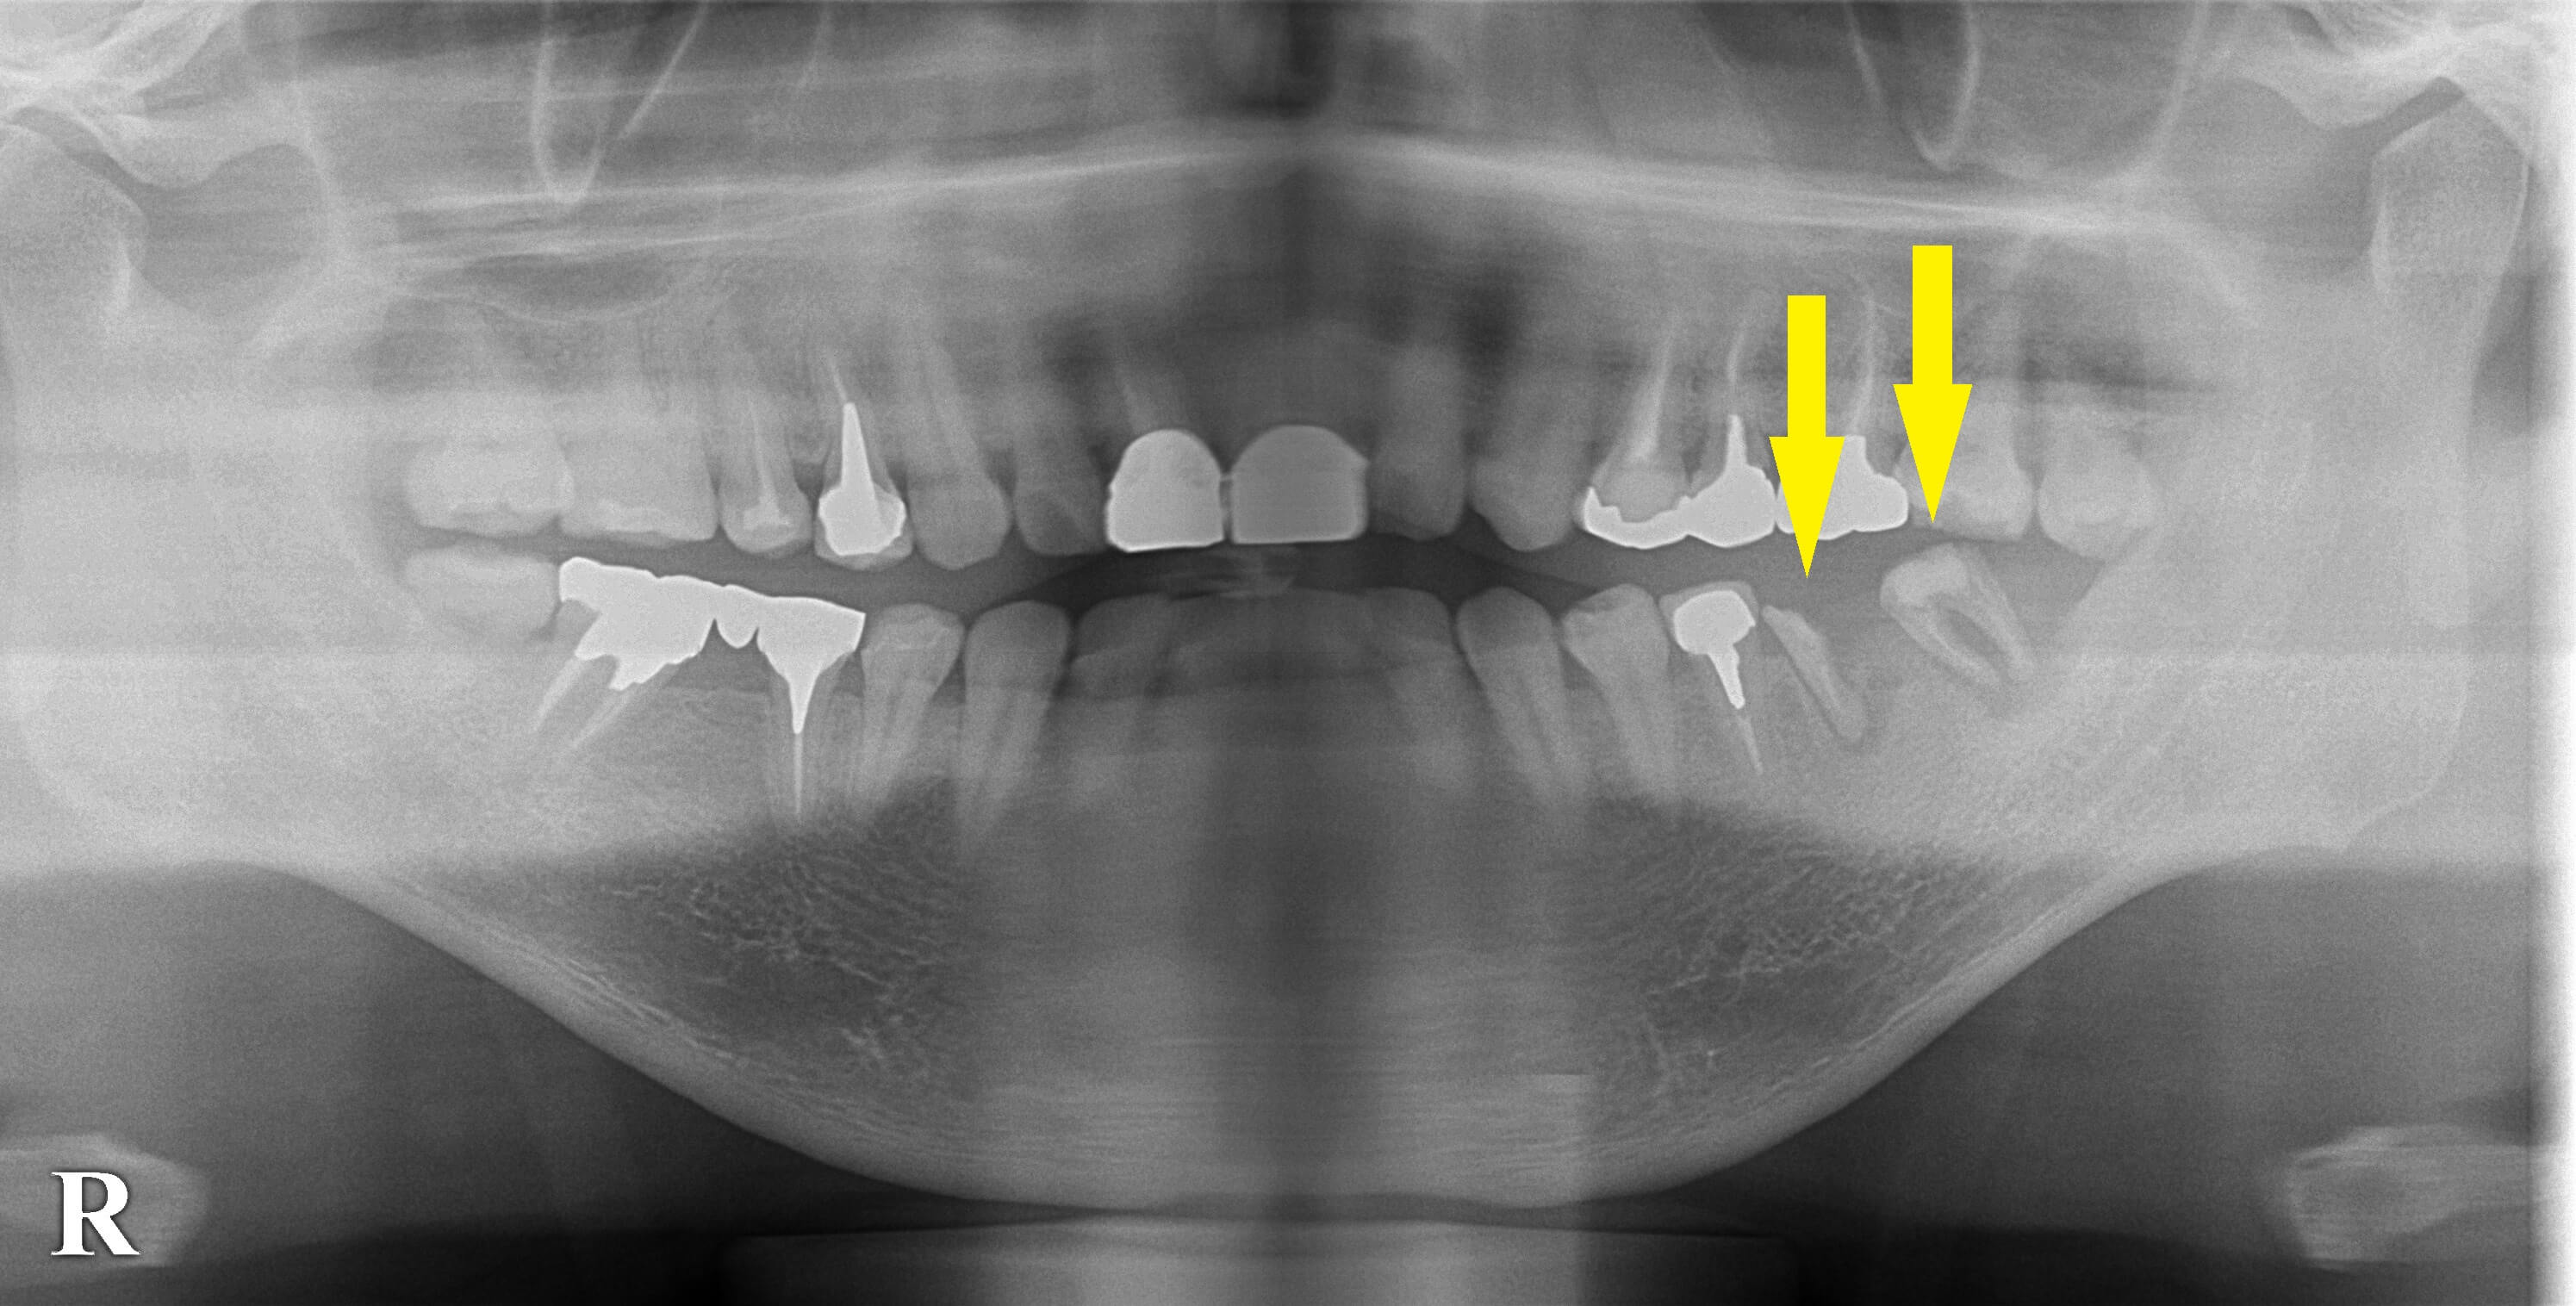

左下顎臼歯に装着されていたブリッジが外れてしまい、支えになっていた歯がボロボロで相談にお出でになりました。

残った歯でもう一度ブリッジは不可能でしたので、抜歯してインプラント治療をお勧めしました。

骨量も問題なく、患者様もインプラントを希望されたので、抜歯して治癒を待ち、本日2本のインプラント埋入術を行いました。